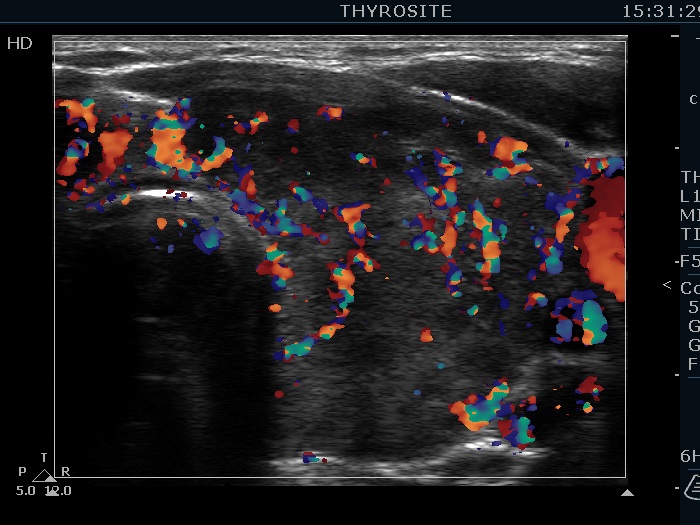

Consecutively operated patients with autoimmune thyroid disease - case 17 (1573) (ultrasonographic picture 8)

Left lobe, longitudinal scan, color Doppler mode.